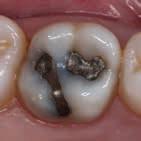

En dybtliggende amalgam-misfarvning udgør en af de mest vanskelige udfordringer ved udskiftning af restaureringer. Transcend Universal Body farven blev anvendt til at erstatte amalgamen, uden brug af blokeringsmateriale. Bemærk, hvor fremragende farven blender ind i den bevarede crista obliqua.

Før Efter